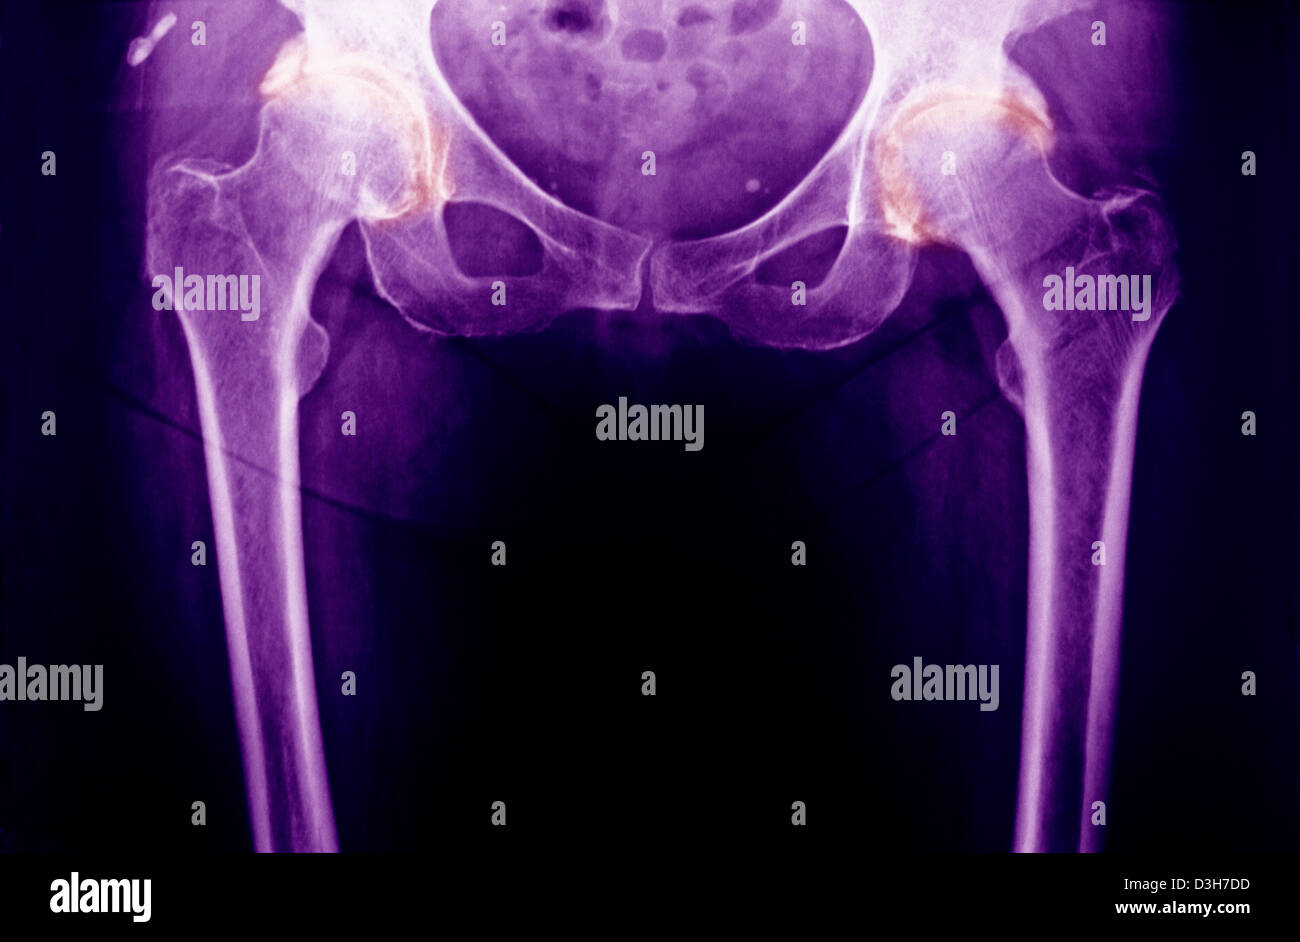

Xray showing arthritis of the hip, arthritis is a joint disease that Hip Arthritis On Xray Osteoarthritis (oa) is the most common disease of the hip joint seen in adults. What is the imaging process for hip and knee osteoarthritis? Diagnosis can be made with. Different grading schemes are described for. Osteoarthritis of the hip can be graded according to its severity. The diagnosis of oa is based on a combination of radiographic findings of joint. Hip Arthritis On Xray.

ARTHRITIS OF THE HIP, XRAY Stock Photo Alamy Hip Arthritis On Xray Different grading schemes are described for. The diagnosis of oa is based on a combination of radiographic findings of joint degeneration and. What is the imaging process for hip and knee osteoarthritis? Osteoarthritis (oa) is the most common disease of the hip joint seen in adults. Osteoarthritis of the hip can be graded according to its severity. Hip osteoarthritis is. Hip Arthritis On Xray.